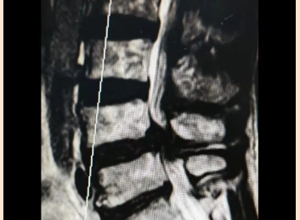

近日,我院神经外科团队成功完成一例高难度手术——为72岁高龄患者实施中央区矢状窦旁脑膜瘤切除及矢状窦修补重建术。这标志着我院在复杂颅脑肿瘤诊疗领域取得重大突破,填补了区域技术空白。 术前患者因"左肢体乏力"来院就诊,经检查确诊为"中央区矢状窦旁脑膜瘤"。这个直径约6cm的肿瘤位置极为凶险,不仅位于大脑中央...